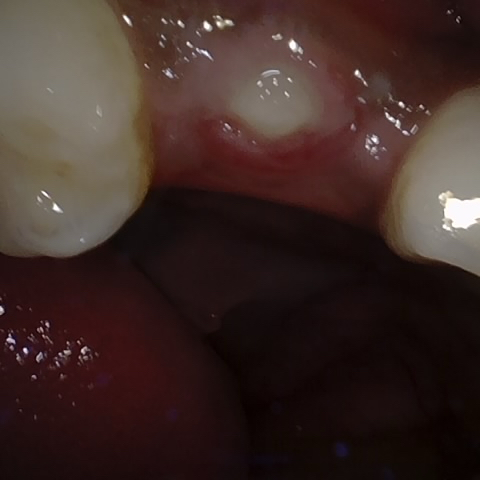

Annotated as "Good"